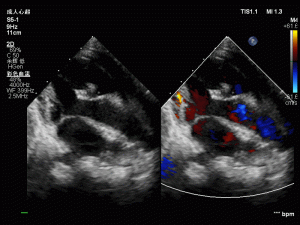

但近年来,由国家心血管病中心+中国医学科学院阜外医院所原创的非放射线引导介入技术,让可吸收封堵器再次成为了研发热点。这种非放射线引导介入技术采用超声引导介入治疗,可在人体内清晰显示可吸收材料,无需金属标记物,解决了可吸收封堵器研发的“关键痛点”。

Pansy®是由上海锦葵医疗研发的一种自膨式可降解室缺封堵器,在塑形性、回弹力和支撑力上都有提升。Pansy®封堵器在超声引导或DSA引导下均可完成封堵器的植入,与金属封堵器的植入方法完全相同,学习曲线短。